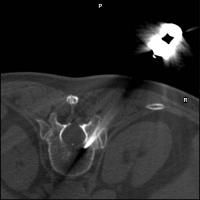

Vertebroplastie - Wirbelkörperpunktion

Abbildung 3: Posterolateraler Zugangsweg.

Keywords:

Lendenwirbelsäule

,

Mineralstoffwechsel

posterolateral

Röntgenbild

Wirbelkörperpunktion